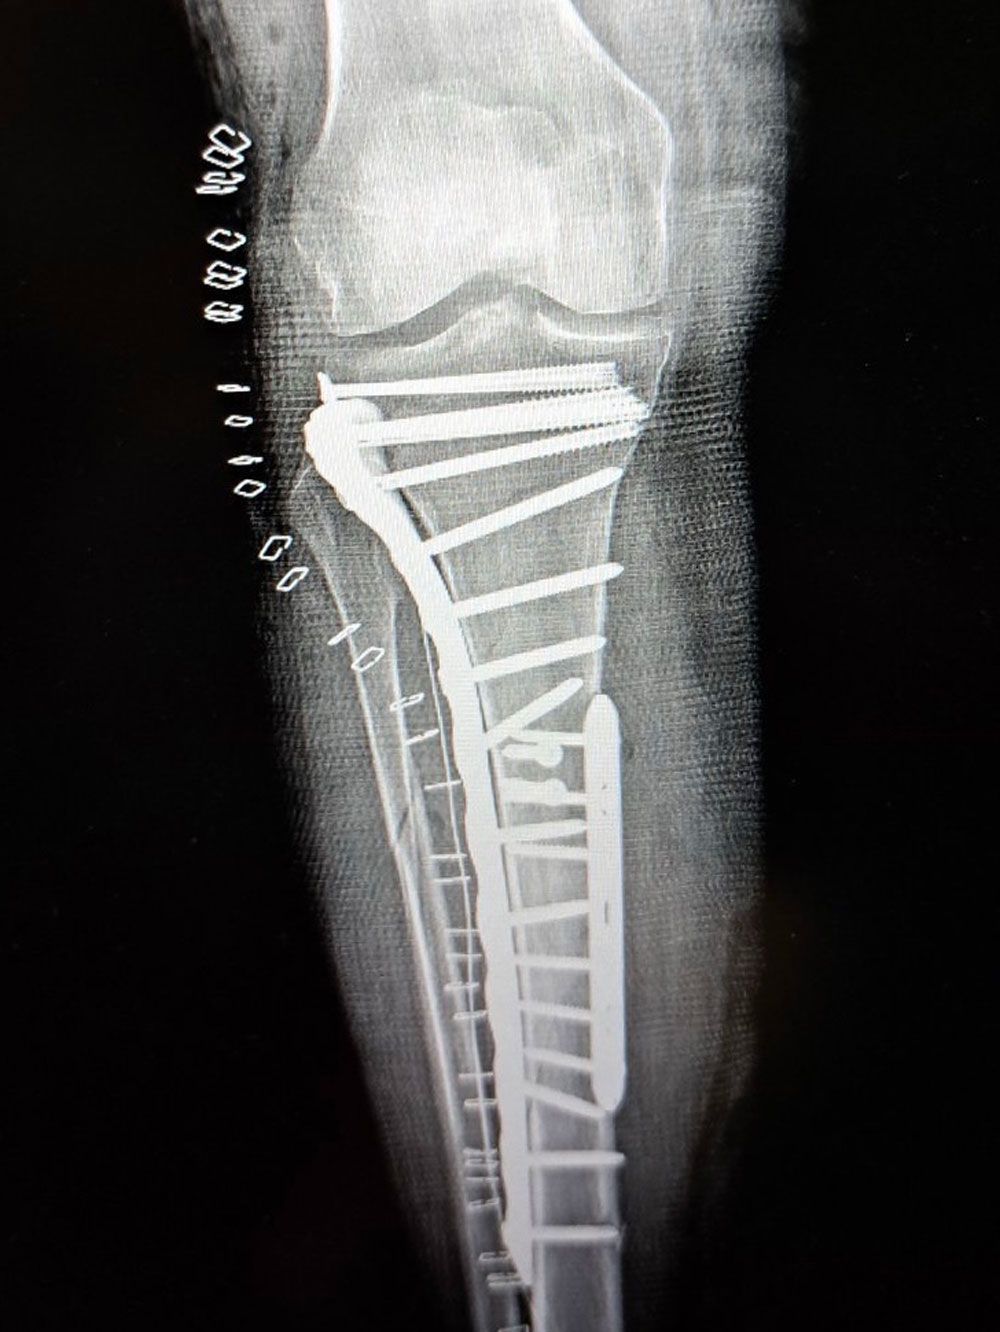

Σοβαρό ενδαρθρικό κάταγμα κνημιαίου πλατώ (Schatzker VI) — υψηλών απαιτήσεων αποκατάσταση με στόχο ανατομική ανάταξη και λειτουργικότητα γόνατος.

Αντιμετωπίσαμε ένα από τα πιο απαιτητικά και σύνθετα τραύματα στην ορθοπαιδική: σοβαρό ενδαρθρικό κάταγμα κνημιαίου πλατώ, Schatzker VI.

Μια επέμβαση υψηλών απαιτήσεων, που απαιτεί ακρίβεια, στρατηγική και απόλυτη προσήλωση στη λεπτομέρεια, με στόχο την ανατομική αποκατάσταση της αρθρικής επιφάνειας και τη διατήρηση της λειτουργικότητας του γόνατος.

Το αποτέλεσμα μας ικανοποιεί.

Gold standard: ORIF (Open Reduction and Internal Fixation)

- Διπλή πλάκα (medial + lateral plating)

- Dual plating (medial + lateral plating)